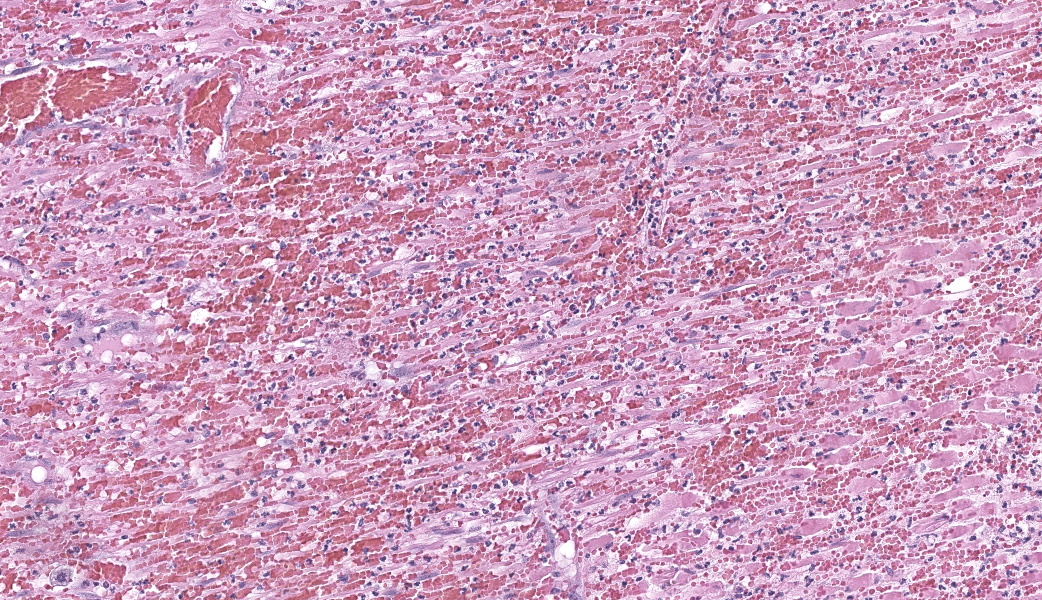

Findings are very similar in all cases that were submitted to the diagnostic laboratory.In all samples from the grossly discolored and swollen segment there was transmural necrosis of the intestine with extensive hemorrhage extending into the mesenteric fat. In the adjacent viable intestine there was eosinophilic infiltration of variable intensity. There was multifocal necrosis of mesenteric fat and, in some sections, diffuse eosinophilic infiltration. Large vessels were dilated and many contained thrombi.

Within the media of medium to small sized arteries there were sections (not present in all slides due to the small size of the parasite – but see photomicrographs) of a nematode larva, approximately 100-200 µm in diameter with lateral allae and central digestive tract. These features are consistent with a spirurid of which Spirocerca is the most likely in our region. Foci of necrosis with hemorrhage were observed in the media of some arteries, where no larvae were identified.

Acute transmural necrotizing eosinophilic enteritis and eosinophilic peritonitis with arterial mesenteric thrombi and rare intralesional nematode larvae (spirurid)Contributor's Comment:

- Mesentery: Arteritis and periarteritis, necrotizing and eosinophilic, chronic, multifocal, severe, with arterial thrombi and rare larval spirurids.

- Small intestine: Enteritis and peritonitis, necrotizing and eosinophilic, chronic, regionally extensive, severe.